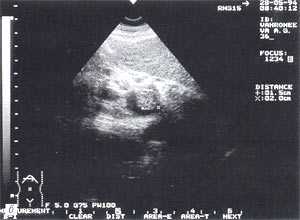

- увеличение размеров поджелудочной железы (рис. 1) - отмечено в 88% случаев. Нормальные размеры поджелудочной железы: головка 3-4,5 см; тело 2,5 - 3 см; хвост 3-4 см;

- увеличение расстояния между задней стенкой желудка и передней поверхностью поджелудочной железы свыше 3 мм и достигающее 10 - 20 мм, что характеризует отек парапанкреатических тканей, отмечено в 53% наблюдений (рис. 1);

Рис. 1. Острый панкреатит, деструктивная форма. Увеличение размеров поджелудочной железы, нечеткость контуров, увеличение расстояния между задней стенкой желудка и поджелудочной железы.